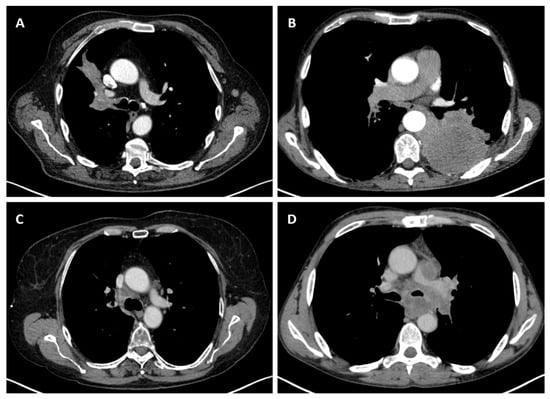

Considering the exclusion criteria previously mentioned, a total of 58 patients were analysed in this study, in which 26 cases were pathologically proven to be adenocarcinoma (Figure 1), 22 cases were shown to be squamous cell carcinoma (Figure 2), and 10 cases were shown to be small cell lung cancer (Figure 3).

Figure 3.

Axial CT of four different cases of small cell lung cancer: (A) right hilar mass with segmental atelectasis and expansion into the right main bronchus; (B) left voluminous mass with central necrosis, pleural invasion and periaortic extension; (C) small-sized central right tumour with paratracheal location; and (D) central left tumour with important mediastinal invasion involving the pulmonary trunk, left pulmonary artery, left main bronchus, and oesophagus.